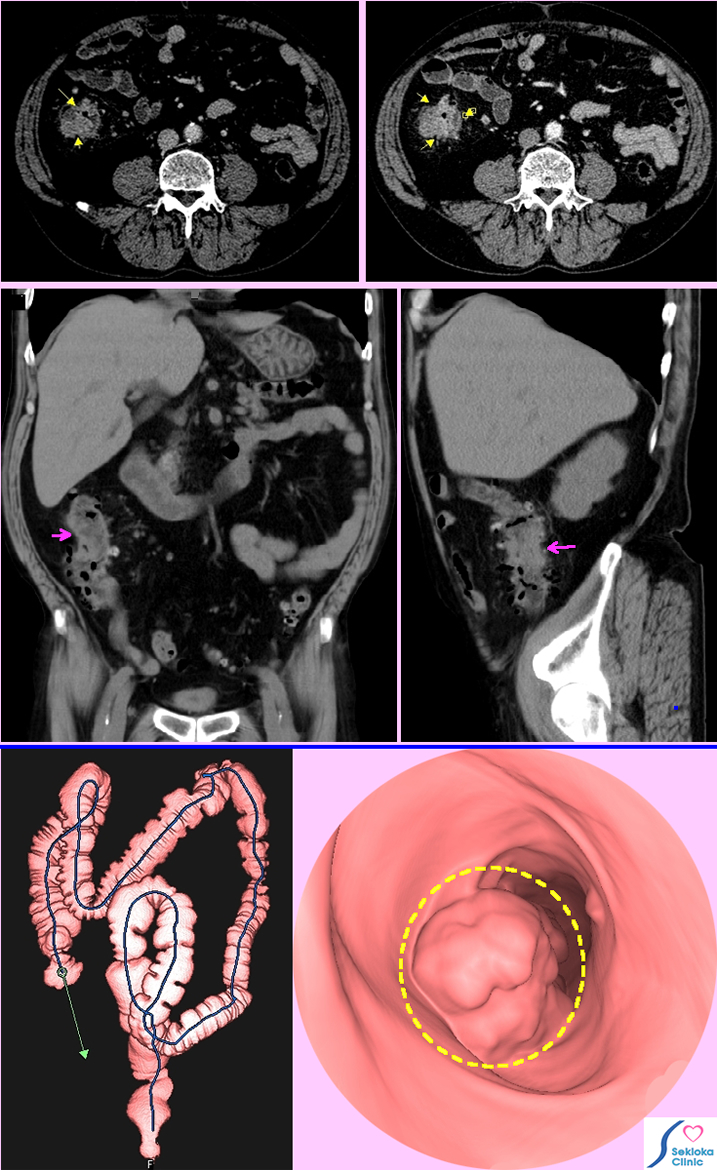

| 自覚症状 | 添付画像の例は 自覚症状なし。肝臓、胆嚢の造影CT検査時、偶然みつかりましたが、一般的にはお腹がはる感じ、便秘、血便などで検査される。 |

| 診断 | 自覚症状が出る前に早期診断を行うことが 転移などを回避でき重要です。大腸がん健診では 便に血液が出ていないか検査し、陽性なら大腸ファイバースコピー、注腸造影、2012年新しい検査法として大腸内に二酸化炭素を入れ、MDCTを用いて撮影し3次元画像から診断する方法が保険適応となりました。下段はその仮想大腸内画像の1例で当院の例です。検査時の苦痛が少なく、短時間、安全な検査法です。 |

| 治療 | 手術。早期なら内視鏡的切除が可能な例もあります。掲載画像の上段例は肝臓への転移なく、手術。 |